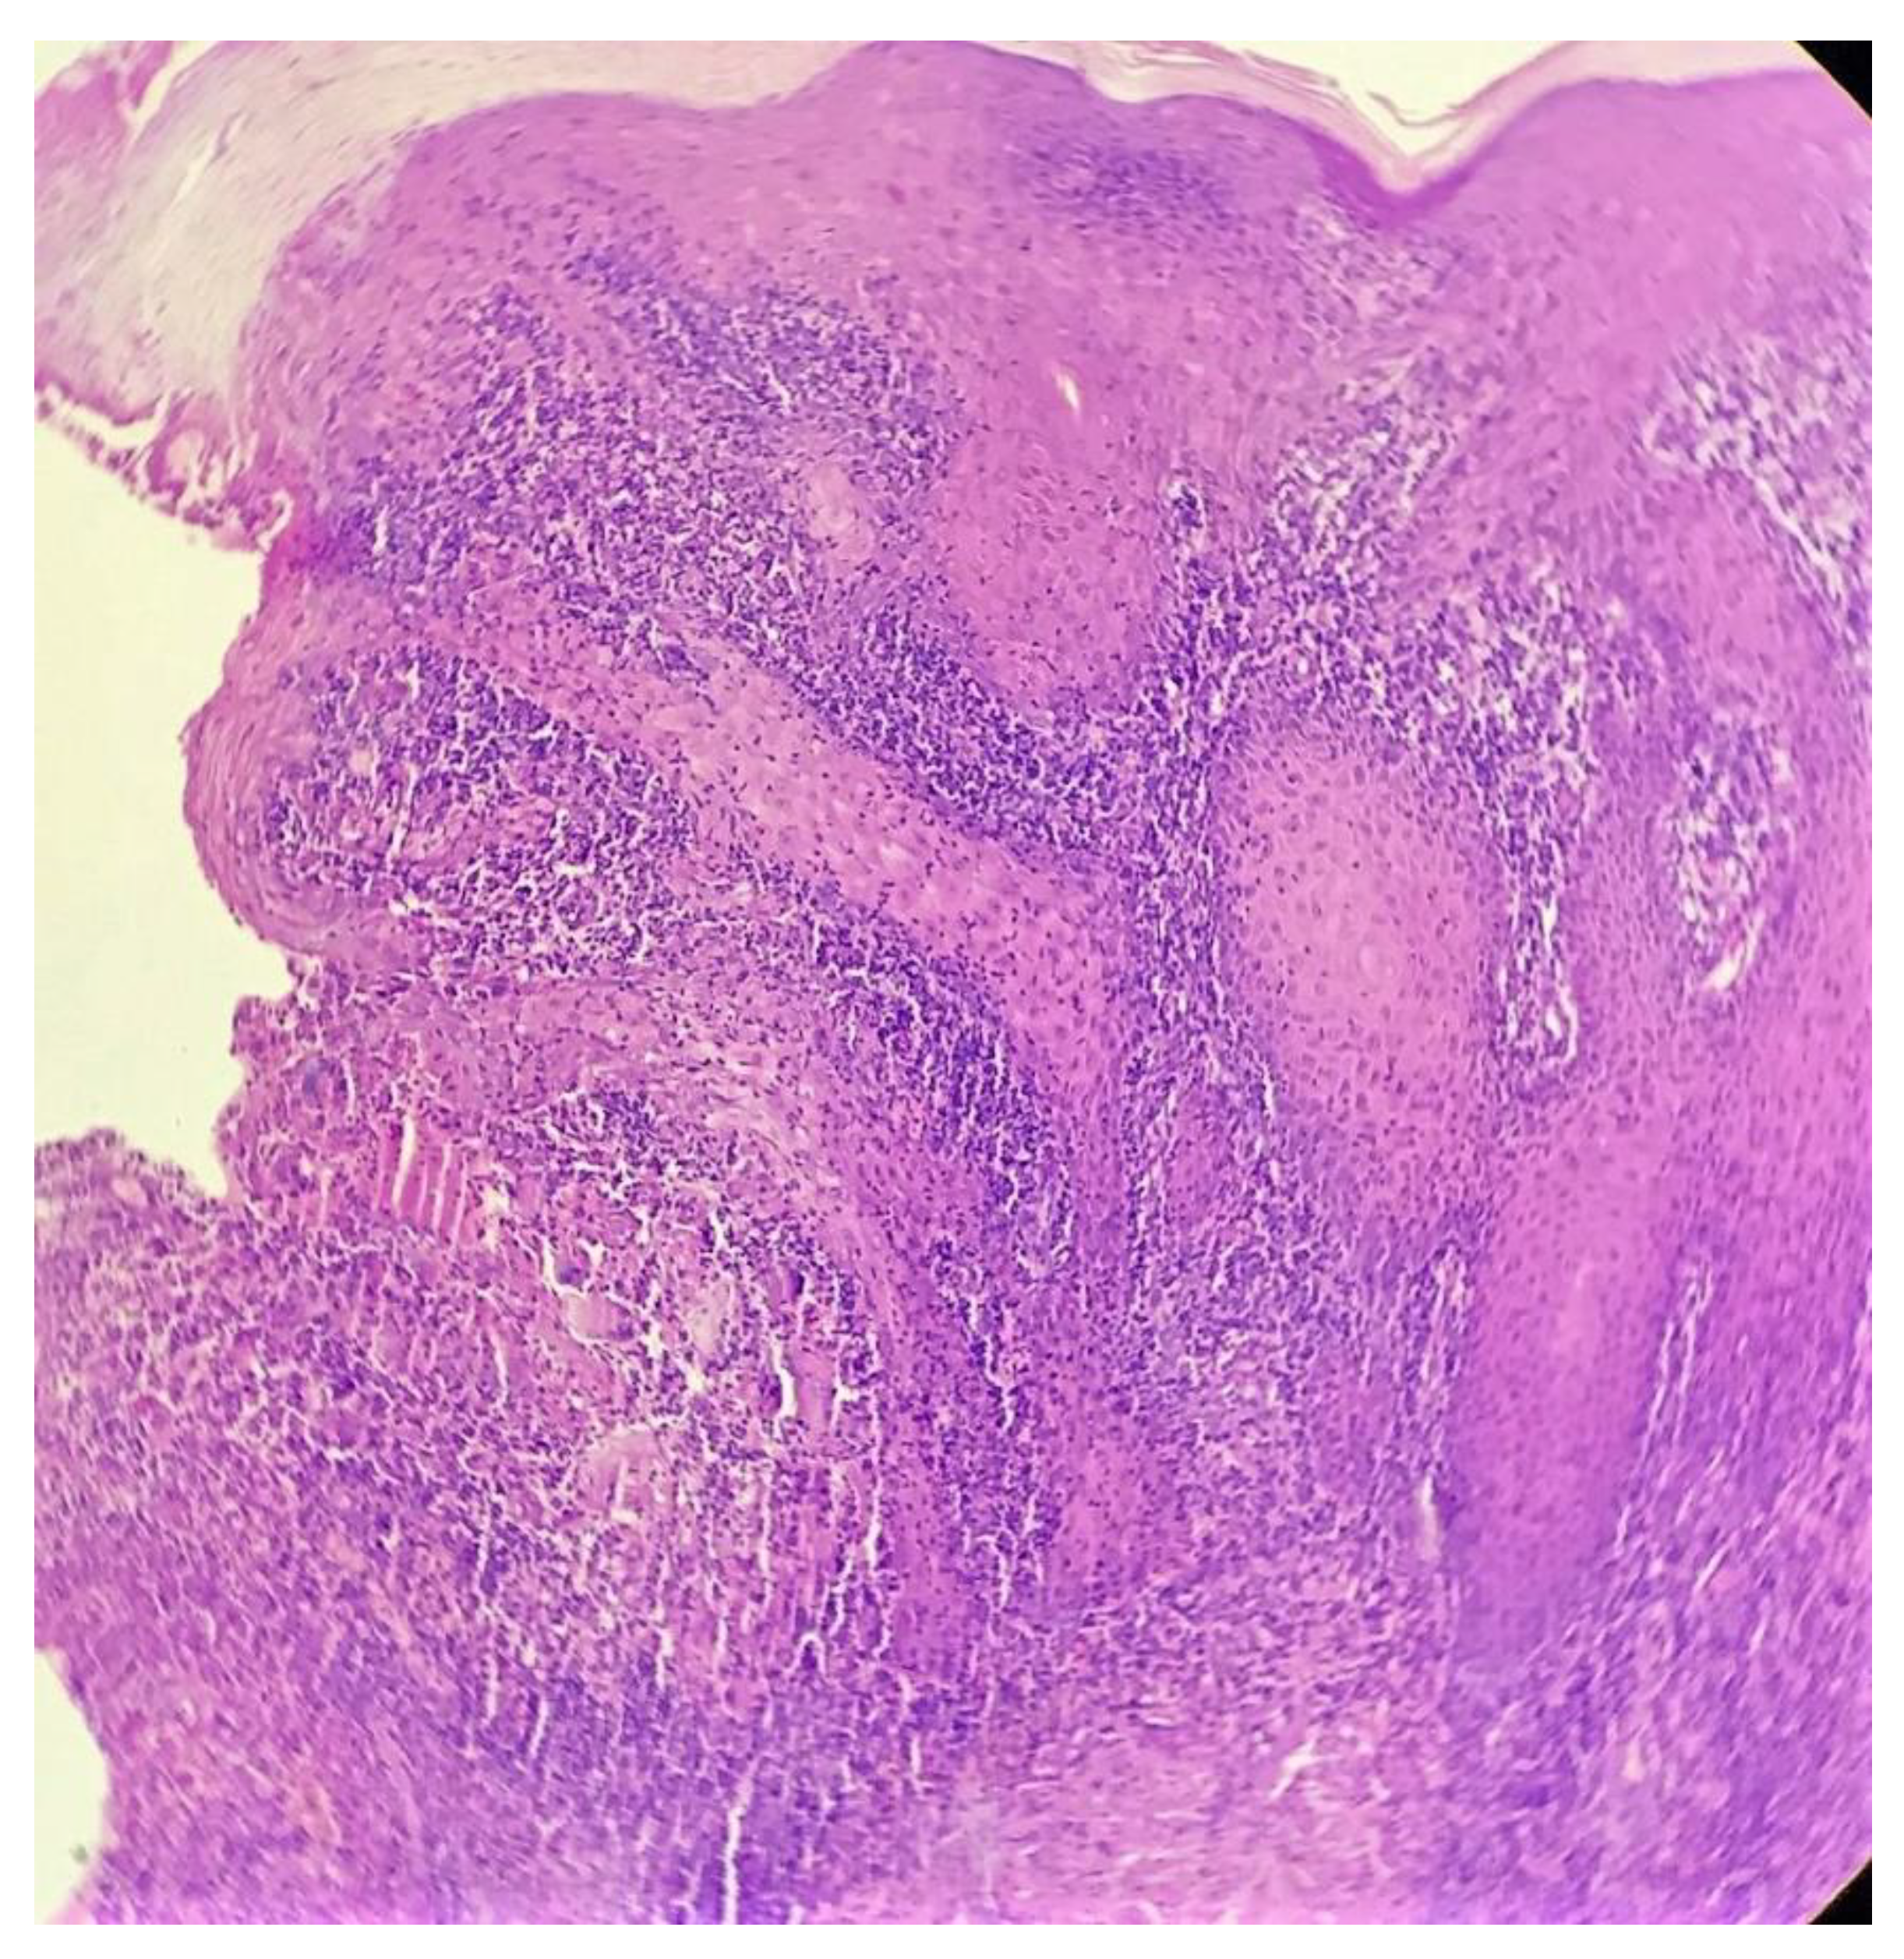

Biopsy showed a dense lichenoid and loose tuberculoid granulomatous infiltrate comprising of epithelioid cells, histiocytes and occasional Langhan’s giant cells, surrounded by lymphocytes and few plasma cells. The granuloma was seen abutting the overlying epidermis, which showed psoriasiform hyperplasia with mild to moderate spongiosis. A compact tuberculoid granuloma was also seen in the deep reticular dermis. Fibroplasia was also seen in the dermis (Figure 2, Figure 3, Figure 4 and Figure 5). The PAS-stained sections were negative for fungal organisms. Zeil–Neelsen stained sections did not reveal any acid-fast bacillus. Based on these features, a diagnosis of lupus vulgaris was favoured and further confirmation by culture study and PCR was advised.

Figure 3. Loose tuberculoid granuloma abutting the overlying hyperplastic epidermis (H&E × 100).